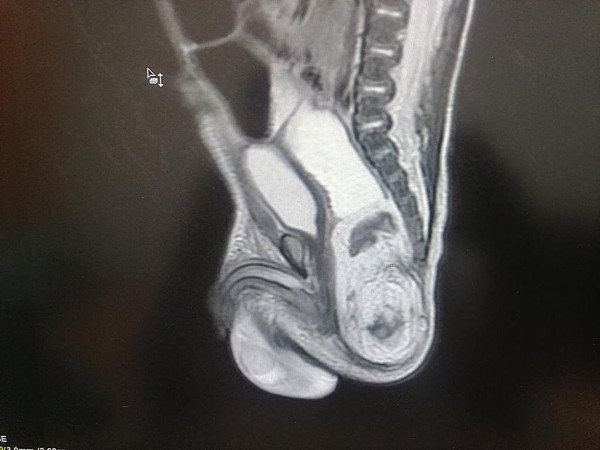

Врачи Кировской областной детской больницы провели сложнейшую операцию по удалению тератомы новорожденному